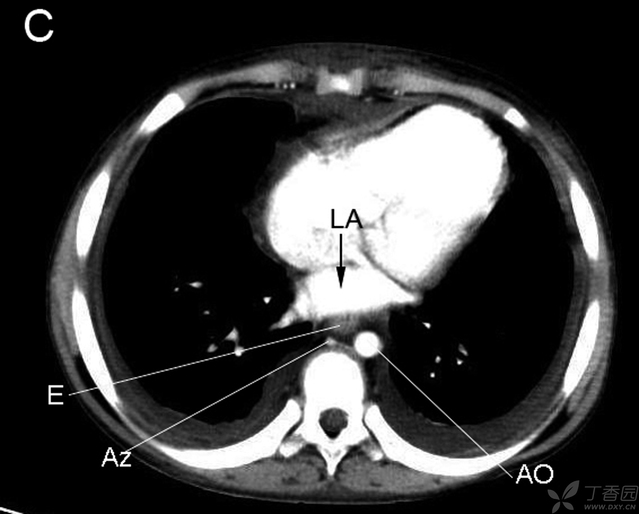

RB右支气管 LA左房 LB左支气管 E食管 AZ奇静脉 AO主动脉

RA右房 RV右室 LA左房 LV左室